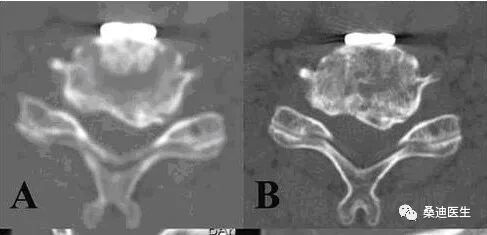

侧隐窝的测量必须满足两个条件:一是必须用骨窗位来测量,二是测量层面必须是完整的椎体层面,即显示出椎弓根的层面。

侧隐窝的测量方法是关节突的内侧缘与椎体后部的连线的长度:

侧隐窝宽窄的判断,小于3mm为肯定狭窄,3mm-5mm为可疑狭窄,大于5mm则不狭窄。